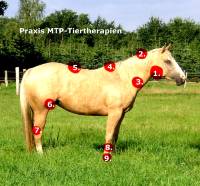

Wie sieht eine Wirbelblockade aus?

Eine Wirbelblockade als grafische Darstellung beim Pferd. Die roten Pfeile zeigen eine Blockierung des TH 18 und LWS 1. Erste Lendennerv schmerzt durch Blockierung und auch Lage des Bauchganglion; dies sind Nervenknoten und gehört zu einer Gruppe zusammenliegender Nervenzellkörper, die in Wirbeltieren von Bindegewebe oder Knochen eingekapselt ist und entweder dicht am Rückenmark oder am Gehirn liegt.

Diese grafische Darstellung einer Wirbelblockade, ist gleich zu setzen, wie bei einem Hund, Mensch und noch anderen Probanten. Diese sehr schmerzhaften Wirbelsäulenbeschwerden sollten behandelt werden, ansonsten werden diese Problemzonen chronisch.

Jeder Wirbel ist für die Versorgung eines Organs zuständig. Kopfschmerzen oder machen sich Magenschmerzen bemerkbar, kann dies auch von der Wirbelsäule ausgehen. Verschiebungen von nur einem Millimeter mit gravierenden Folgen: Wirbelblockaden; Auslöser stechender Schmerzen und Ursache der meisten Rückenprobleme.

Bewegungsapparat Erkrankungen

Die am häufigsten vorkommenden Erkrankungen im Bewegungsapparat beim Pferd und Hund

1.Ohrspeicheldrüse

2. falscher Knick in der Beizäung

3. Unterhals

4. Kissing Spines BWS

5. Kissing Spines LWS

6. Überdehnte Kniebänder

7. Spat

8. Überbeansruchung der Sehnen/ Bänder der Vorhand

9. Strahlbeinlahmheit